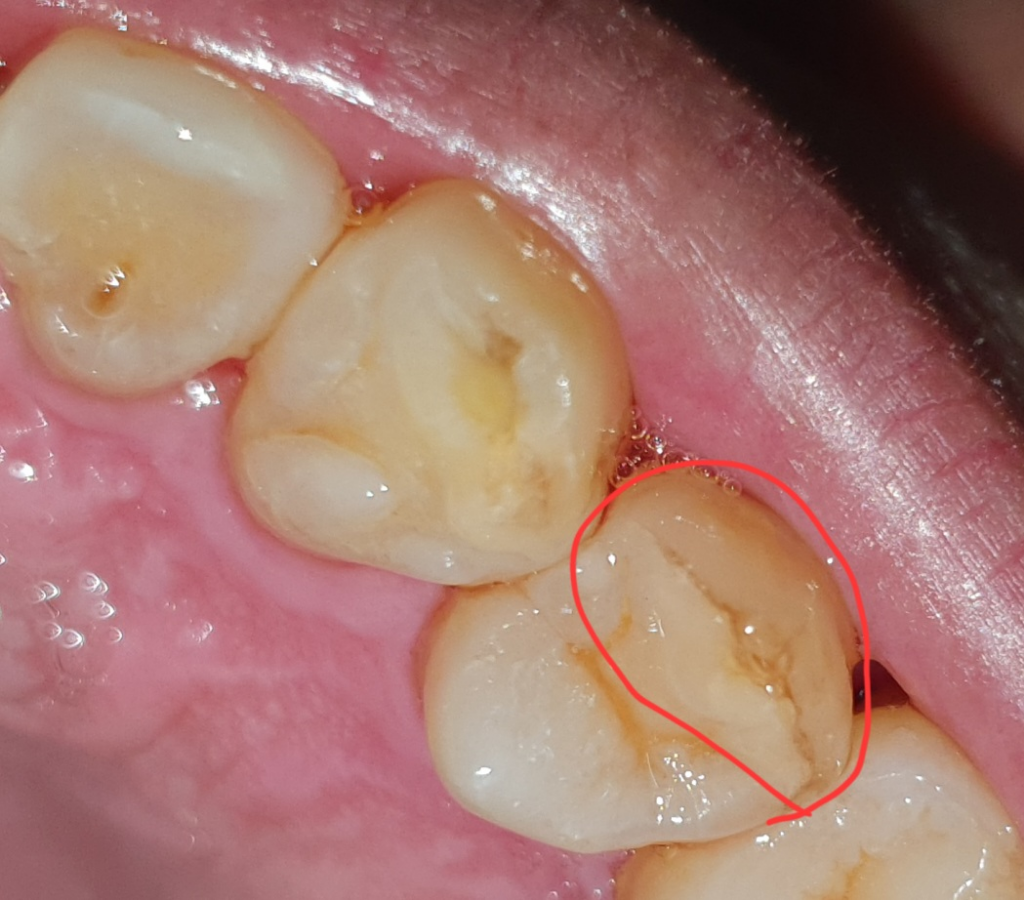

사진 속 빨간 부분 금이 간 것인가요 아니면 변색된 것인가요?

현재 통증은 딱히 없는데 금 간 것이면 무조건 크라운을 씌워야하는지 아니면 다른 방법이 있는지 궁금합니다.

사진 상으로는 금이 갔는지 판단하기 어렵습니다. 여러가지 검사를 통해서 해당 부위의 금 정도를 판단해야 하며 미세한 금이라면 단순히 사진이나 검사만으로는 힘들 수 있습니다. 정확한 판단을 위해서는 치과 방문 후 검사를 해야 합니다.